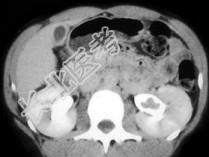

- 单项选择题该患者因血尿急诊,根据所提供图像, 最可能的诊断是 ( )

A、肾结石

B、血块

C、移行细胞癌

D、息肉

E、以上都不是